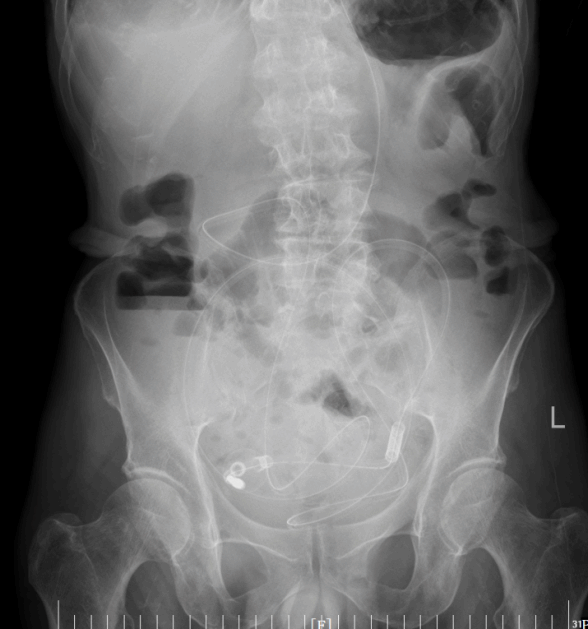

王大爷因腹痛、腹胀一周,伴呕吐、停止排气排便四天,被紧急送入我院肿瘤外科二病区。经影像学检查,王大爷被明确诊断为低位小肠梗阻。这意味着梗阻发生在小肠末端,肠道内容物完全无法下行,大量消化液和气体在肠腔内积聚,肠壁被持续撑胀,随时可能缺血坏死、穿孔,引发致命性腹腔感染。

入院后,贺伯伟主任团队立即为王大爷采取禁食禁水、胃管减压、抑酸等常规保守治疗措施。但几天过去,老人的症状始终没有明显改善,腹胀、腹痛较前加剧。经院内相关科室会诊,认为王大爷年事已高,还合并多种基础疾病及食管肿瘤,整体身体状况较差,根本无法耐受常规外科手术的创伤,同时家属也不愿承担手术风险。

导管开始工作后,积聚的肠内容物被持续引出,腹胀腹痛的症状一天天缓解。老人的肠道功能慢慢恢复,复查腹平片显示梗阻情况明显好转。在护理团队的精心照料下,老人从卧床不起到能下地活动,从禁食禁水到逐渐恢复饮食,一天天好起来。2月24日,王大爷顺利出院,重新回归了正常生活。